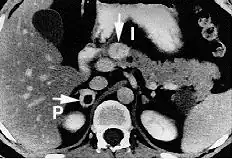

Pheochromocytoma

Pheochromocytoma is a disease in which a catecholamine secreting tumor develops.[2][20] Specifically, norepinephrine and epinephrine are secreted by these tumors, either continuously or intermittently.[21] The excess release of these catecholamines increases central nervous system stimulation, thus causing blood vessels to increase in vascular resistance, and ultimately giving rise to hypertension.[20] In addition, patients with these rare tumors are often subject to headaches, heart palpitations, and increased sweating.[2]

Phenoxybenzamine, a nonselective α1 and α2 blocker, has been used to treat pheochromocytoma.[21] This drug blocks the activity of epinephrine and norepinephrine by antagonizing the alpha receptors, thus decreasing vascular resistance, increasing vasodilation, and decreasing blood pressure overall.[21]